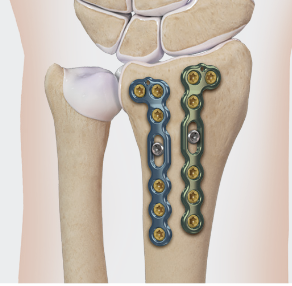

Dorsal distraction plating

Internal radiocarpal distraction

- unreconstructable distal radius fractures

- early weight bearing in poly trauma patients

- osteoporotic bone

Advantage - no pin site infection from external fixation

Disadvantage - need to remove plate at 3 - 4 months once fracture united

Technique

Fixation to 2nd or 3rd metacarpal first

- 2nd metacarpal: under 2nd extensor compartment

- 3rd metacarpal: under 4th extensor compartment

- reduce / distract joint

- +/- additional radius fixation